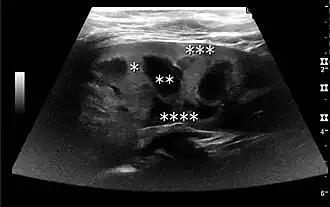

Cortical thickness should be estimated from the base of the pyramid and is generally 7–10 mm. If the pyramids are difficult to differentiate, the parenchymal thickness can be measured instead and should be 15–20 mm (Figure 3). The echogenicity of the cortex decreases with age and is less echogenic than or equal to the liver and spleen at the same depth in individuals older than six months. In neonates and children up to six months of age, the cortex is more echogenic than the liver and spleen when compared at the same depth.[1]

Figure 3. Measures of the kidney. L = length. P = parenchymal thickness. C = cortical thickness.[1]